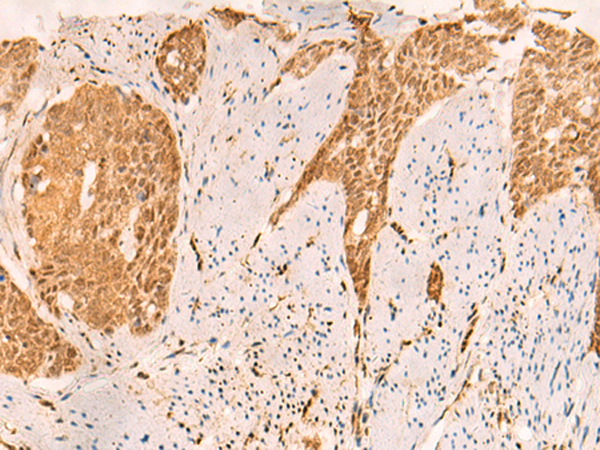

(The image is immunohistochemistry of paraffin-embedded Human esophagus cancer tissue using 47638(SETD1A Antibody) at dilution 1/25.(Original magnification: 200))

(The image is immunohistochemistry of paraffin-embedded Human gastric cancer tissue using 47638(SETD1A Antibody) at dilution 1/25.(Original magnification: 200))